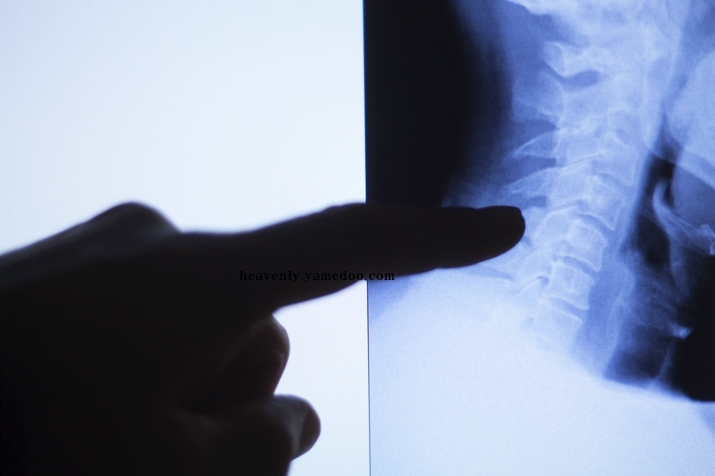

목디스크는 경추 즉 목뼈 사이의 디스크가 빠져나오거나 뼈조직이 목으로 지나가는 척추 신경을 압박하여 통증을 발생시키는 것입니다. 발생 원인으로 알아보면 평소 바르지 못한 자세, 접촉사고, 충격여파 등 다양한 요인들이 있습니다.